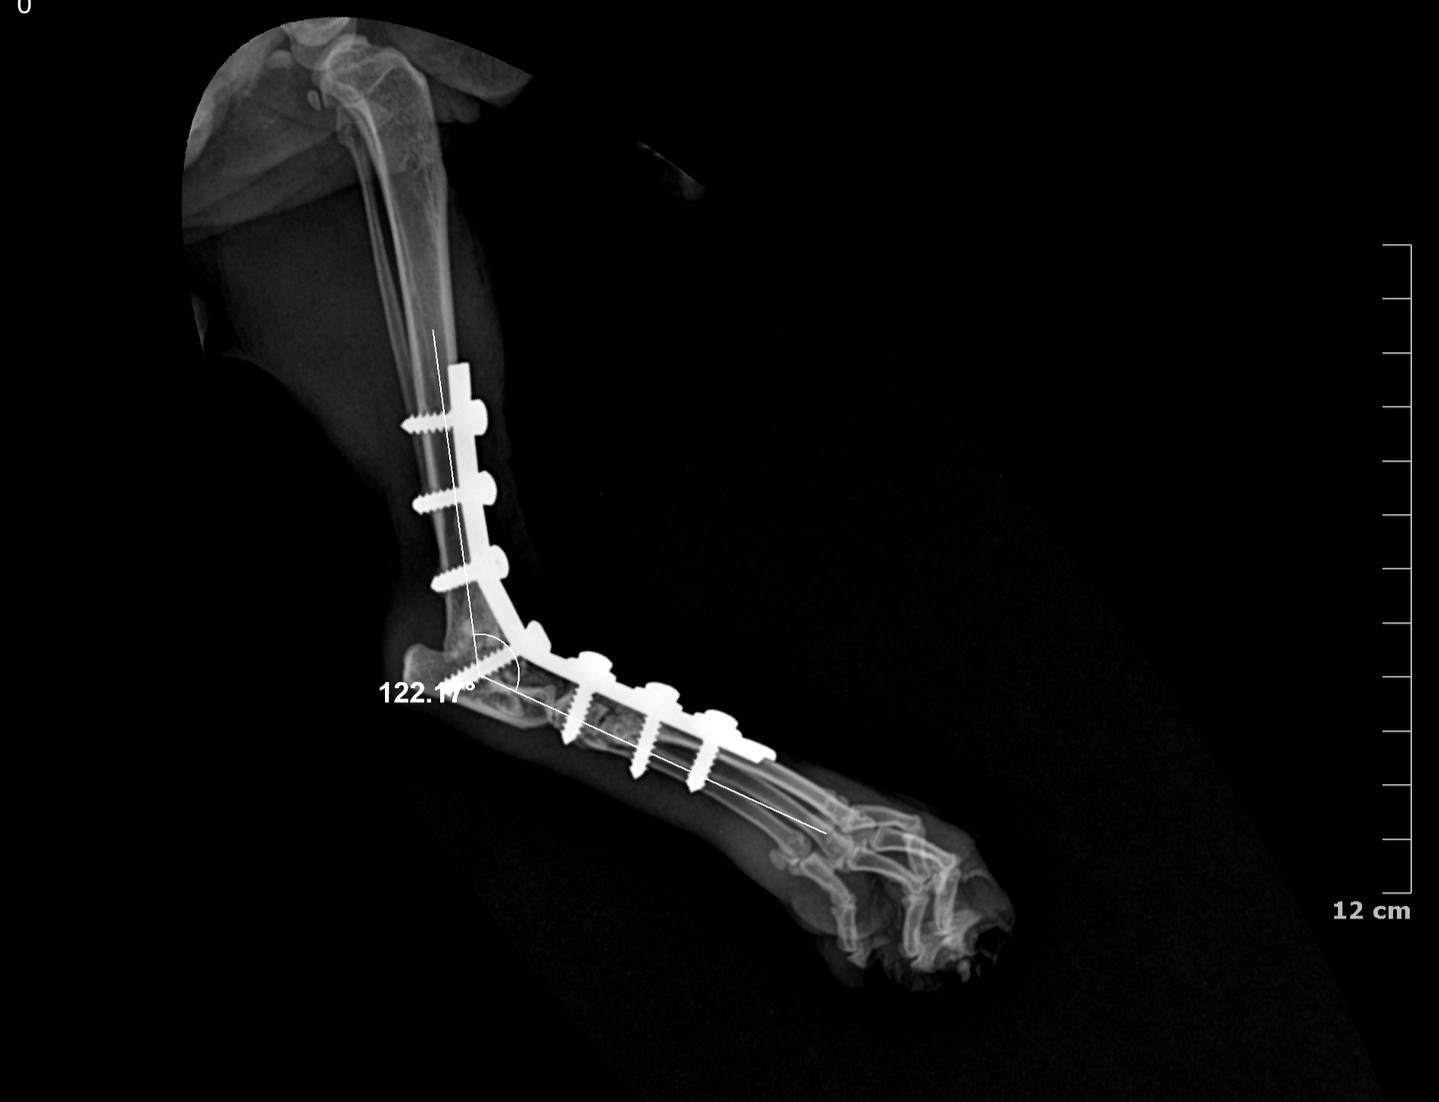

Pan-tarsal Arthrodesis

Pantarsal arthrodesis is a surgical procedure that involves the fusion of all joints within the tarsus (hock) including the tibiotarsal, intertarsal, and tarsometatarsal joints into a single solid bone unit

It is performed to restore a stable, pain-free limb when the tarsal joint complex is irreparably damaged or unstable

Surgical Treatment: Pantarsal Arthrodesis